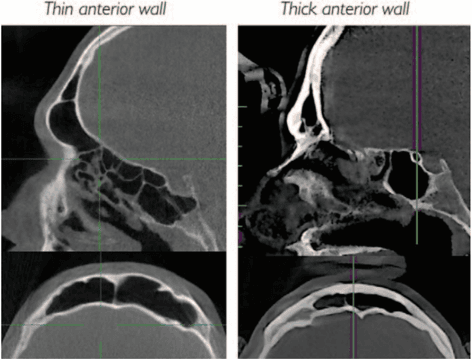

Transnasal endoscopic microfractured fat injection in glottic insufficiency

A. M. Saibene, C. Pipolo, R. Lorusso, S. M. Portaleone, G. Felisati, B-ENT, 2015